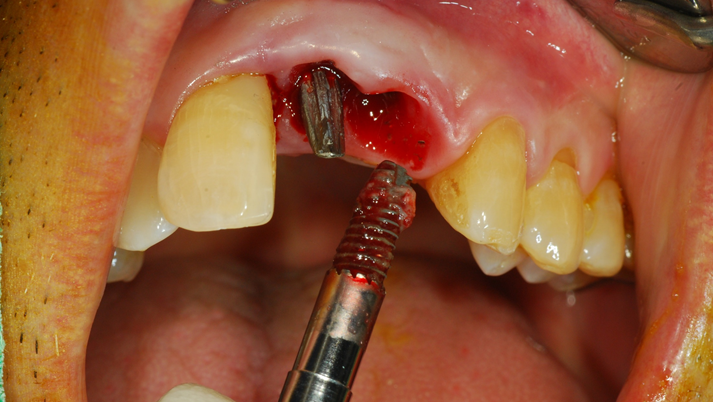

“Achieving a clean surface is the key to treating peri-implantitis!Using a titanium or NiTi brush for the decontamination process along with proper GBR can successfully restore the peri-implant environment. ”

Clinical case: Peri-implantitis treatment case using titanium or NiTi brush

- Courtesy of Dr. Dae-Hee Lee, South Korea -

Dr. Dae-Hee Lee,Maxillary Anterior,Peri-implantitis,Bone regeneration,Aesthetic zone,#21,#22,GBR,Titanium Brush Set

Titanium Brush Set